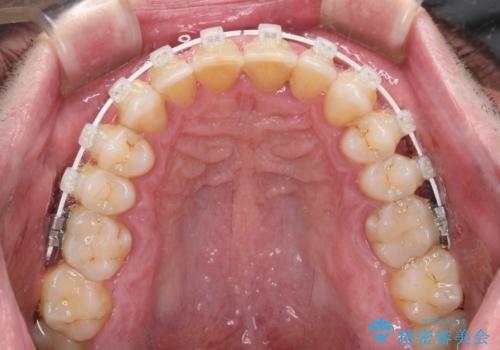

- 審美装置

前歯の非接触改善は、インビザラインの得意とするところですが、マウスピース矯正は絶対に継続できないとのことで、ワイヤー装置にて矯正治療を行うこととしました。